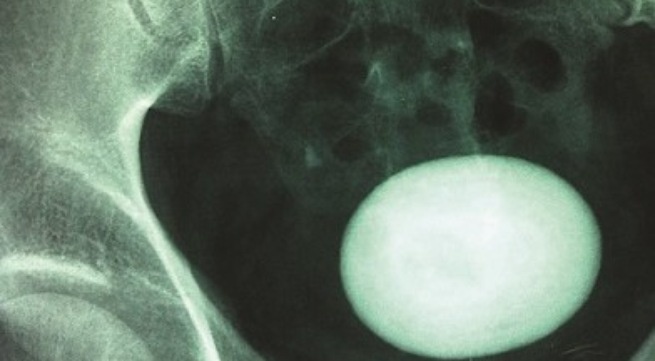

![]() |

| Sỏi bàng quang trên phim. |